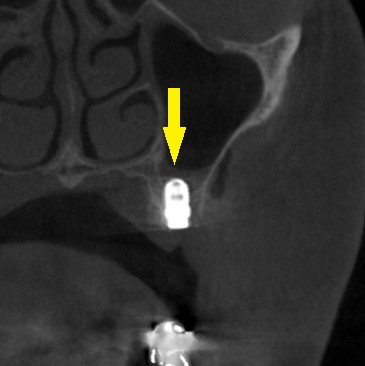

CTを撮ってみると、写真上段のように、第一小臼歯部は骨幅が狭く、第二小臼歯部は骨の高さが不足していました。

下の写真、下段が手術後のCTです。

第一小臼歯では外側に人工骨が白く写り、第二小臼歯では上方の空洞の底が持ち上げられるようになっているのが、確認できます。